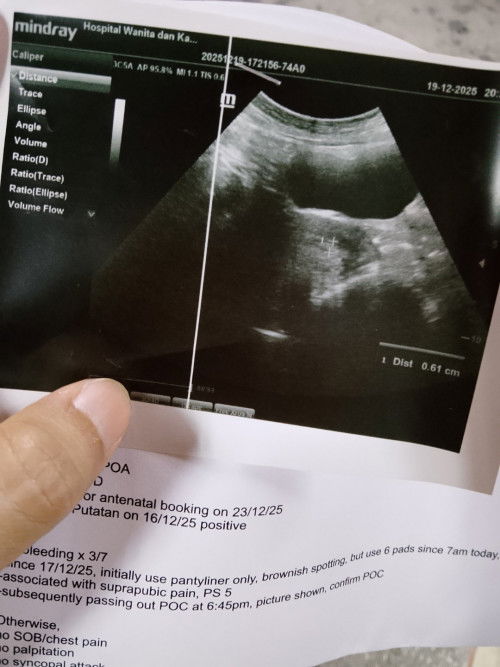

17hb - 18hb bleeding dctr KK pun dah scan kosong kantung tak jumpa , Harini bleeding sampai 6 pad 6:38pm keluar ketulan daging , terus g hospital dctr scan atas bawa tak nampak jadi doctor sahkan keguguran 8:45pm ( 19/12/2025 )